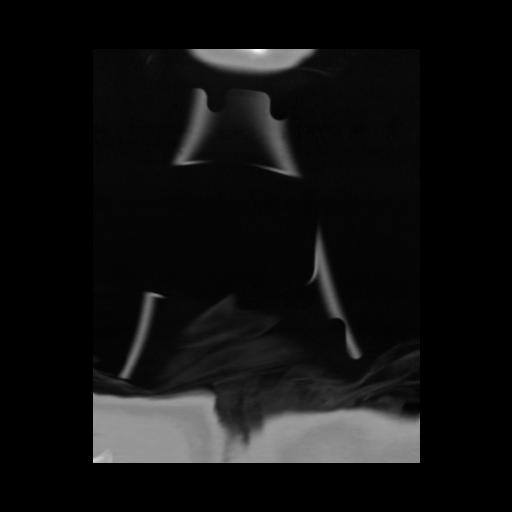

13 P.BLANDAS,,Coronal,2.000,P.BLANDAS,Coronal,